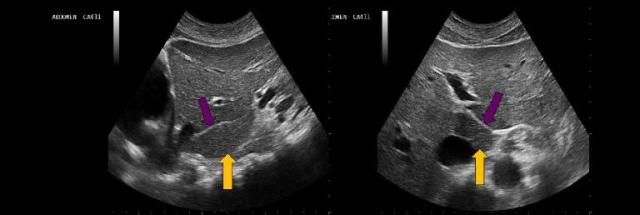

What structure is indicated by the yellow arrow?

main lobar fissure |

The yellow arrow on the images represents which of the following structures?

|

The purple arrows point to which of the following liver structures?

ligamentum teres |